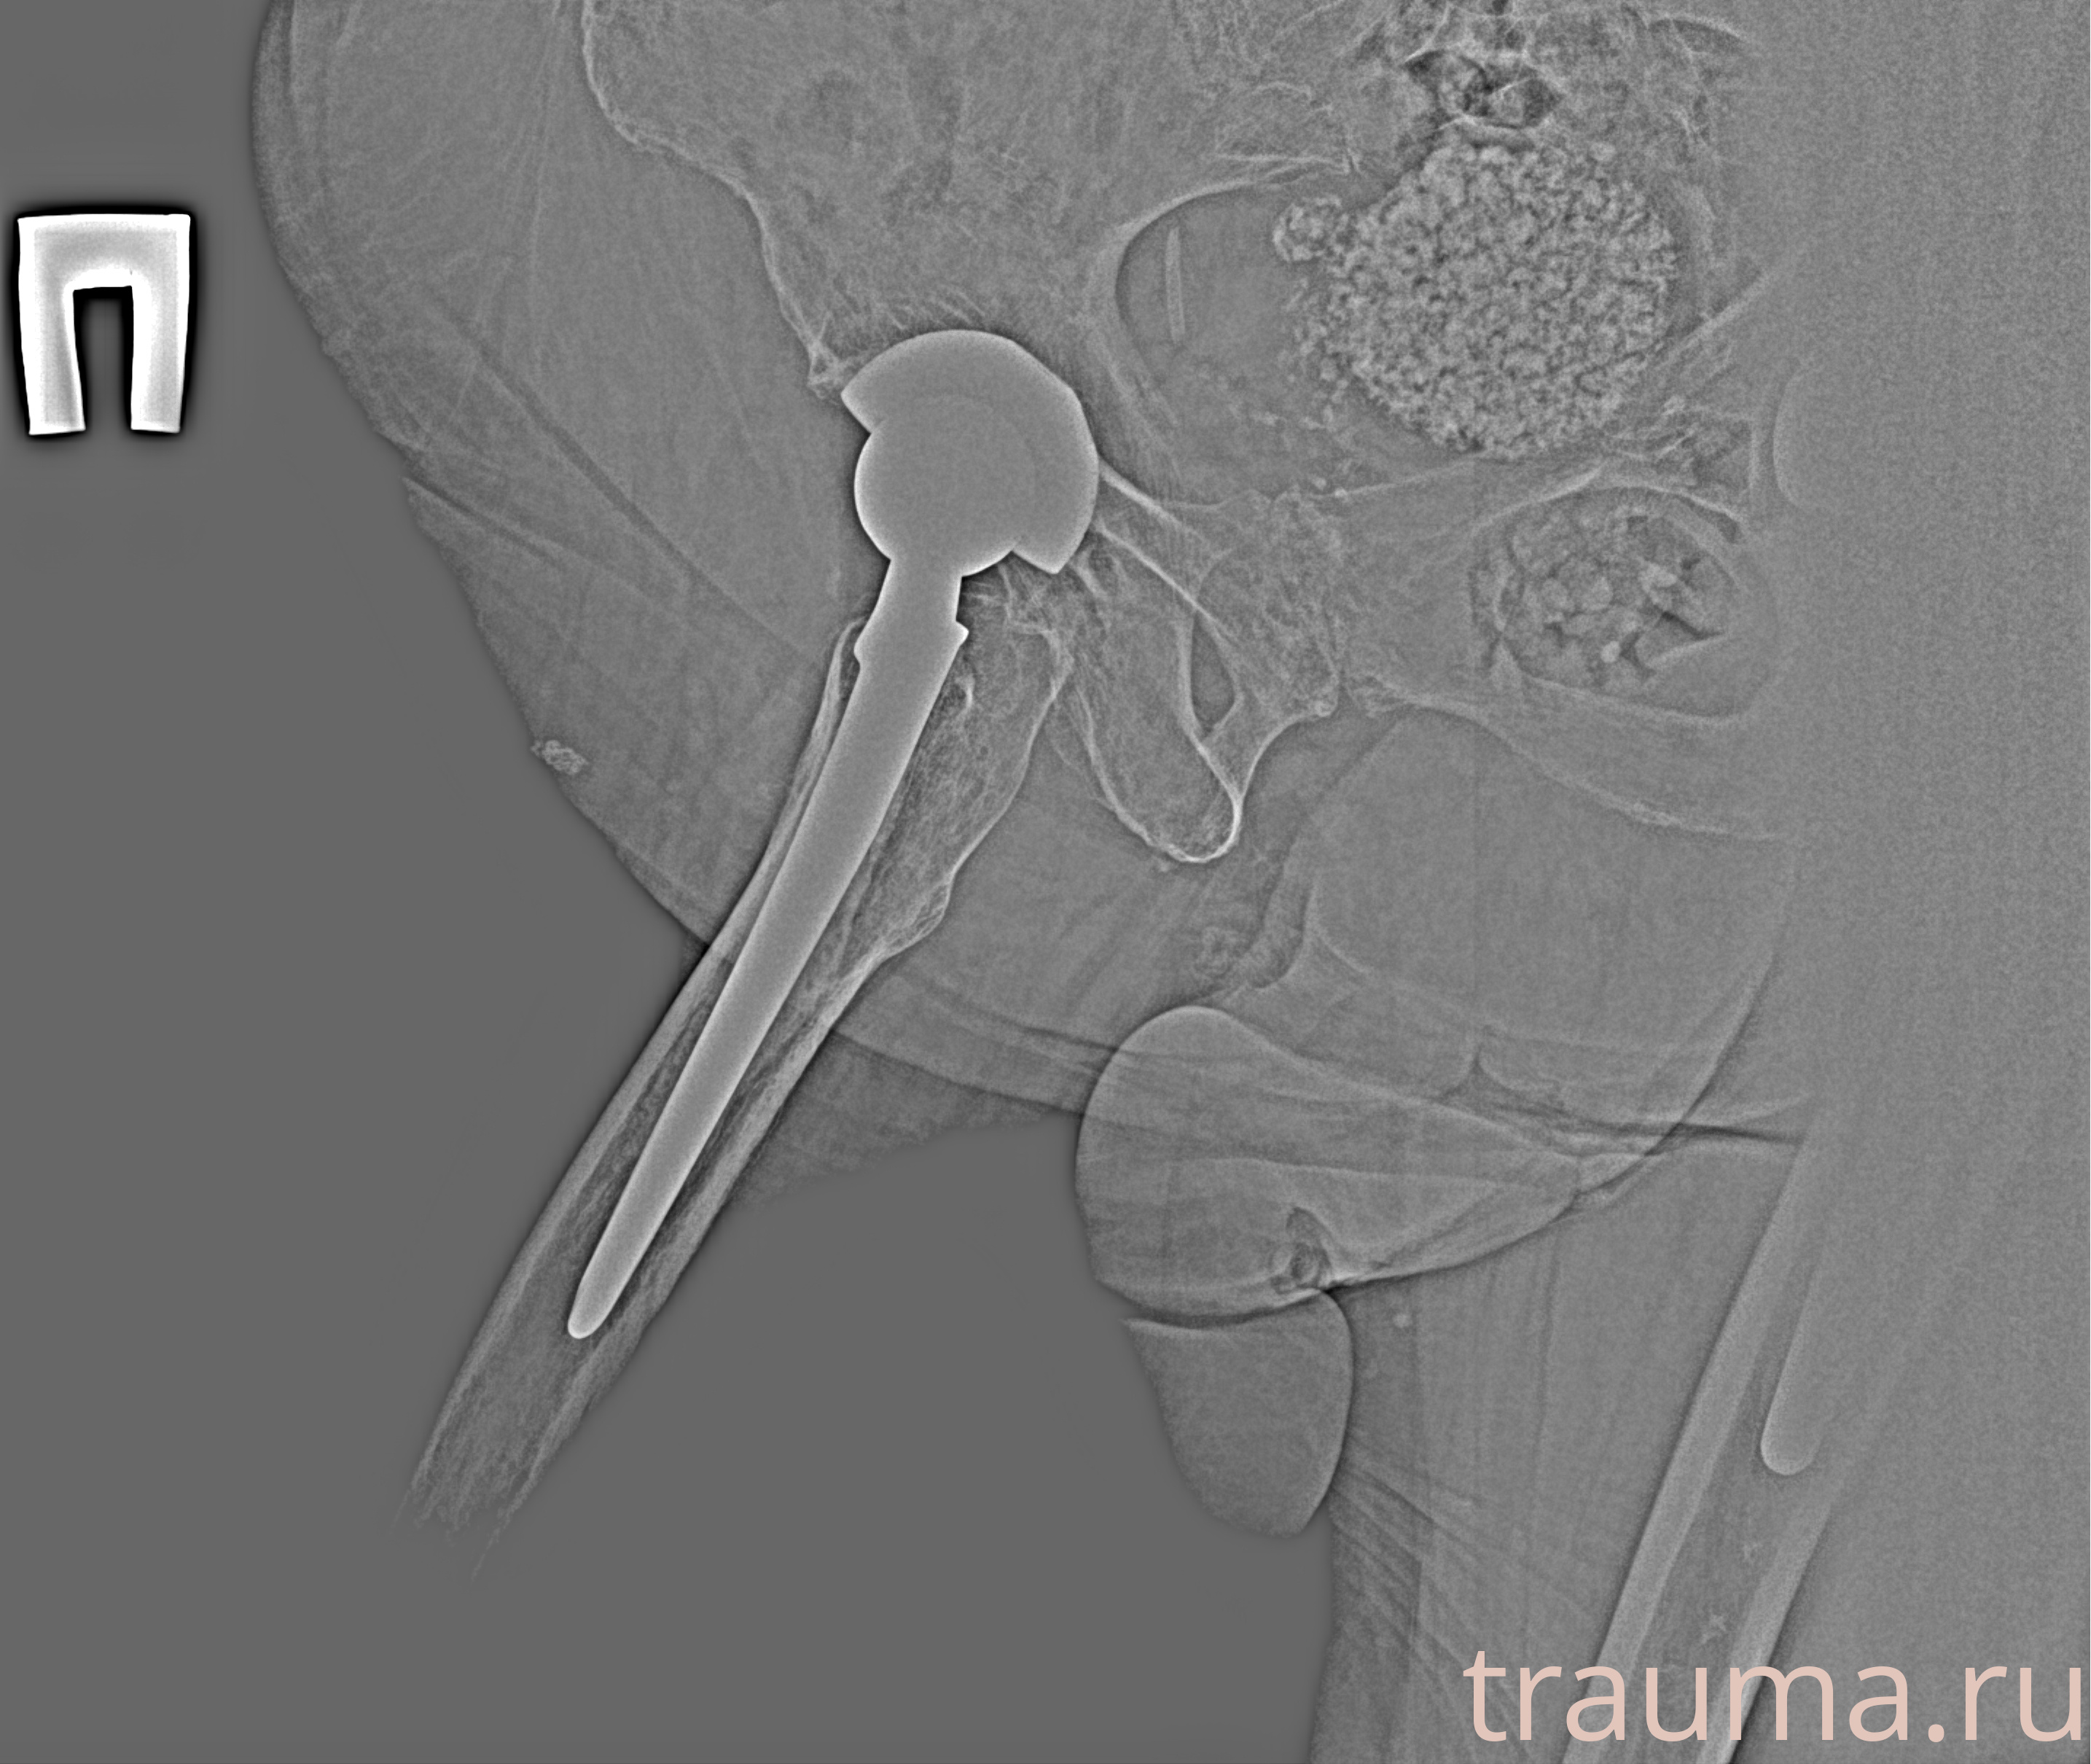

Рентгенограммы

Рентген на дому: по вашему адресу приезжает врач-рентгенолог, травматолог-ортопед с мобильным рентгеновским аппаратом, проводит диагностику травмы или заболевания, делает необходимые рентгенограммы, дает рекомендации по дальнейшему лечению. Получить качественные снимки в домашних условиях возможно благодаря уникальной методике, разработанной МосРентген Центром для института  Склифосовского

Яркость: 1   Контраст: 1   Инвертировать: 0 Увеличение: 1

Перетаскивайте мышь вверх/вниз для контраста, влево/право для яркости. Прокрутка колесом изменяет масштаб. Нажмите Сбросить для возврата к исходному изображению. При увеличении держите мышь в той области, которую хотите рассмотреть.